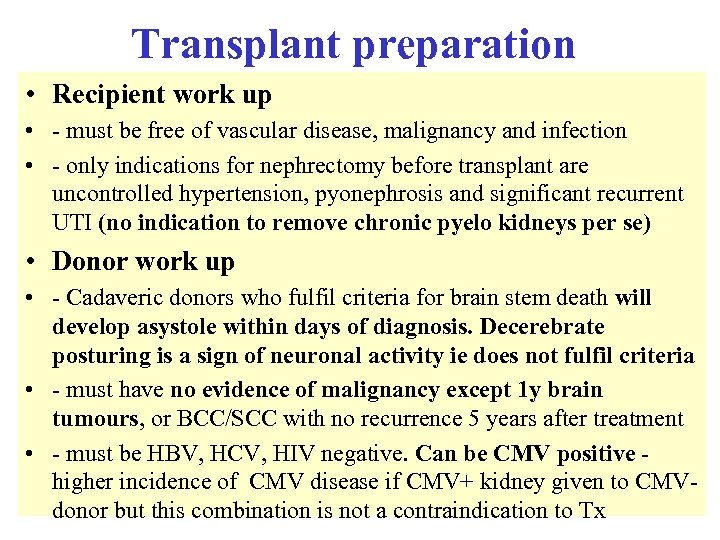

Transplant preparation • Recipient work up • - must be free of vascular disease, malignancy and infection • - only indications for nephrectomy before transplant are uncontrolled hypertension, pyonephrosis and significant recurrent UTI (no indication to remove chronic pyelo kidneys per se) • Donor work up • - Cadaveric donors who fulfil criteria for brain stem death will develop asystole within days of diagnosis. Decerebrate posturing is a sign of neuronal activity ie does not fulfil criteria • - must have no evidence of malignancy except 1 y brain tumours, or BCC/SCC with no recurrence 5 years after treatment • - must be HBV, HCV, HIV negative. Can be CMV positive higher incidence of CMV disease if CMV+ kidney given to CMVdonor but this combination is not a contraindication to Tx

Transplant preparation • Recipient work up • - must be free of vascular disease, malignancy and infection • - only indications for nephrectomy before transplant are uncontrolled hypertension, pyonephrosis and significant recurrent UTI (no indication to remove chronic pyelo kidneys per se) • Donor work up • - Cadaveric donors who fulfil criteria for brain stem death will develop asystole within days of diagnosis. Decerebrate posturing is a sign of neuronal activity ie does not fulfil criteria • - must have no evidence of malignancy except 1 y brain tumours, or BCC/SCC with no recurrence 5 years after treatment • - must be HBV, HCV, HIV negative. Can be CMV positive higher incidence of CMV disease if CMV+ kidney given to CMVdonor but this combination is not a contraindication to Tx